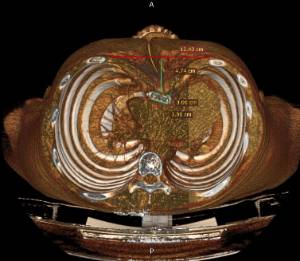

Los datos médicos del paciente, más la exploración clínica realizada por el equipo de cirugía, junto a un análisis pormenorizado de las imágenes del TAC y las reconstrucciones digitales en 3D de cada tórax realizadas conjuntamente con el equipo de ingenieros de Ventura Medical Technologies, son la base para determinar si la técnica Pectus Up está indicada y como se debe proceder en cada uno de los pacientes.

Con estos datos se selecciona el implante que mejor se ajustar a la anatomía de cada tórax, la ubicación exacta del sistema de elevación y, a su vez, proporciona al equipo quirúrgico un detalle de los pasos a tener en cuenta para llevar a cabo una correcta implantación.

Antes y después de una intervención de Pectus Up.